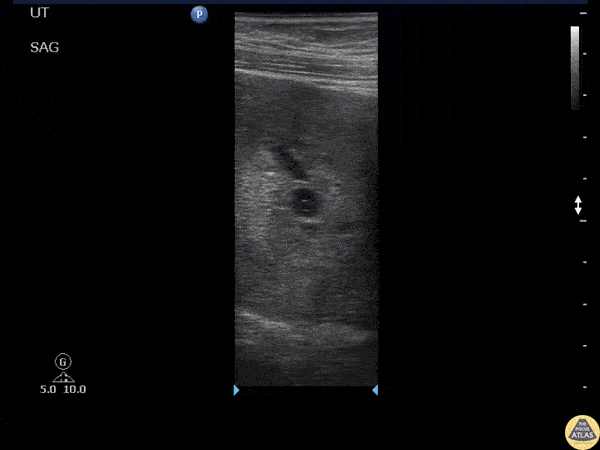

OB/Gyn - Yolk Sac

A transabdominal scan with a curvilinear probe failed to show an intrauterine yolk sac however, when using a linear probe a yolk sac became visible. Image courtesy of Robert Jones DO, FACEP @RJonesSonoEM Director, Emergency Ultrasound; MetroHealth Medical Center; Professor, Case Western Reserve Medical School, Cleveland, OH View his original post here